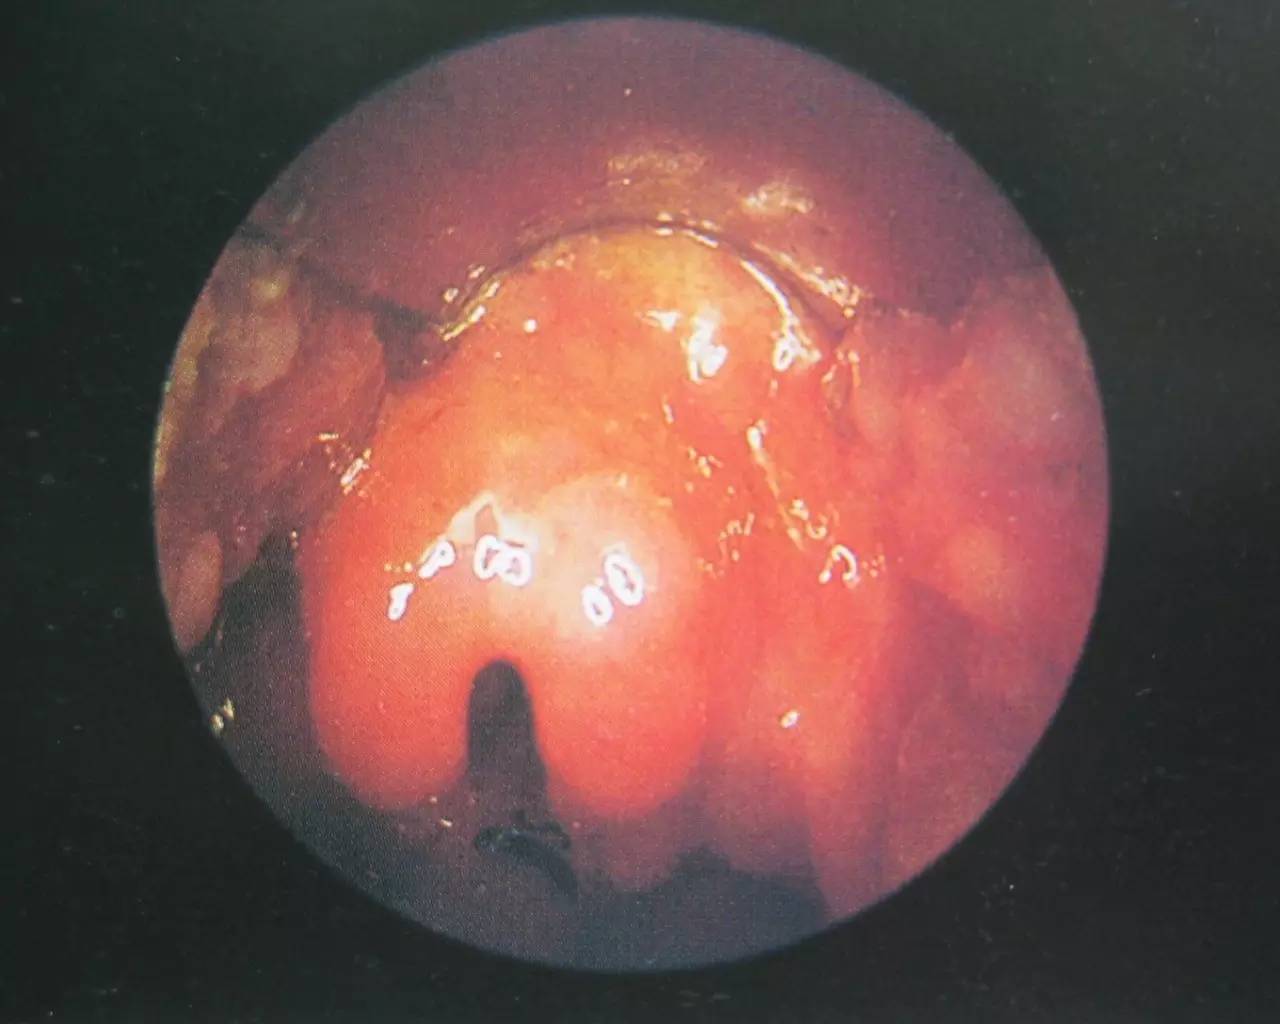

异常会厌

喉镜下,该病人会厌已肿胀如球,如水泡一样,紧贴咽后壁,喉入口已被遮挡。若不及时处理,很有可能一下子呼吸困难窒息而死。

口咽部检查多无明显改变,易被忽略,但是剧烈咽痛无法解释。只要采用间接喉镜检查,即可发现会厌明显充血、肿胀、严重时呈球形。如会厌脓肿形成,红肿黏膜表面可见黄白色脓点。由于肿胀会厌遮盖,声门是看不到的。